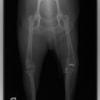

術前正面像

術後左後肢正面像

術前のTPAは左後肢33.1°右後肢26.8°でしたがTPLO実施により左後肢5.5°右後肢12°に矯正されました。